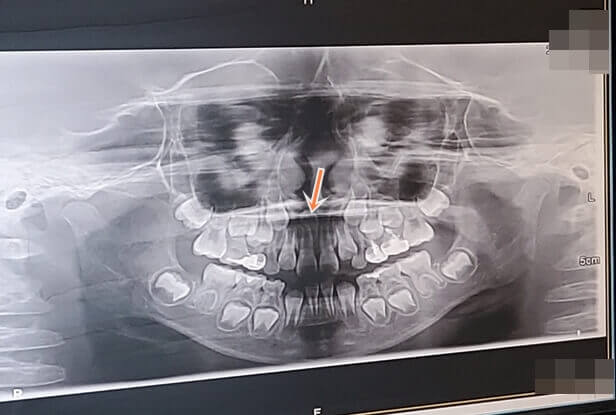

키즈치과에 검진을 받으러 갔다가 듣게 된 아이의 과잉매복치.

만 6세 아이 치과 진료에서 갑자기 알게 된 과잉치

1. 과잉치가 앞니 사이에 거꾸로 있고, 지금 인중쯤 위치해 있는데 두면 더 올라갈 수 있다

2. 아이는 후에 교정이 필요한 치열인데 교정 시 과잉치가 방해가 된다

3. 발치하지 않을 시 뼈가 녹아 낭종이 될 수도 있다

첫 진료는 엑스레이 사진 찍어 확인하고 소아치과에서 진료 후 구강악안면외과로 예약 잡고 큰 어려움 없는 진료였고요.